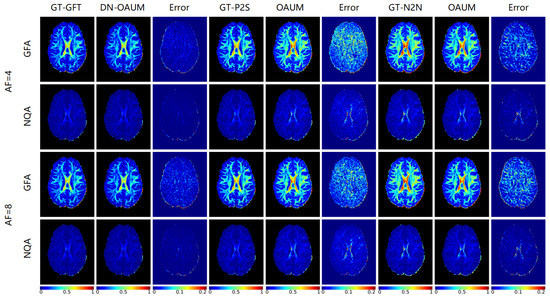

Based on the reconstruction of fiber orientation using HARDI, we calculated the generalized fractional anisotropy (GFA) and normalized quantitative anisotropy (NQA) under different acceleration sampling factors to characterize the diffusion of water molecules in tissues, as shown in Figure 7. The given GFA and NQA results, along with corresponding residual maps, indicate that all models except IDPCNN and ISTANet++ can reconstruct diffusion parametric maps well. Our OAUM model had the closest reconstructed GFA and NQA to the real results, with minimal residual values compared to the other models. Although the NQA image reconstructed by DGDN was close to our method, its reconstructed GFA image was slightly worse. Table 4 and Table 5 provide quantitative indicators that show that, regardless of whether it is at a 4-fold or 8-fold acceleration factor, the OAUM model obtained optimal quantitative evaluation results for both GFA and NQA, i.e., with the lowest RMSEs and the highest PSNRs and SSIMs. This implies that our proposed strategy ensures accuracy in HARDI parametric maps reconstruction under undersampling conditions.

Figure 7. The parametric maps estimated from DWIs at different acceleration factors.

Table 4. RMSE, PSNR, and SSIM of GFA reconstructed from different methods at different acceleration factors.

Table 5. RMSE, PSNR, and SSIM of NQA reconstructed from different methods at different acceleration factors.